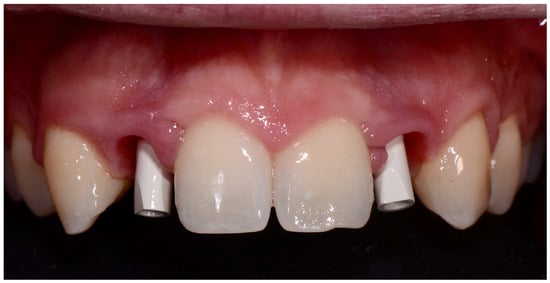

2. Materials and Methods

- 11–12 months: prosthetic finalization and baseline control (T0);